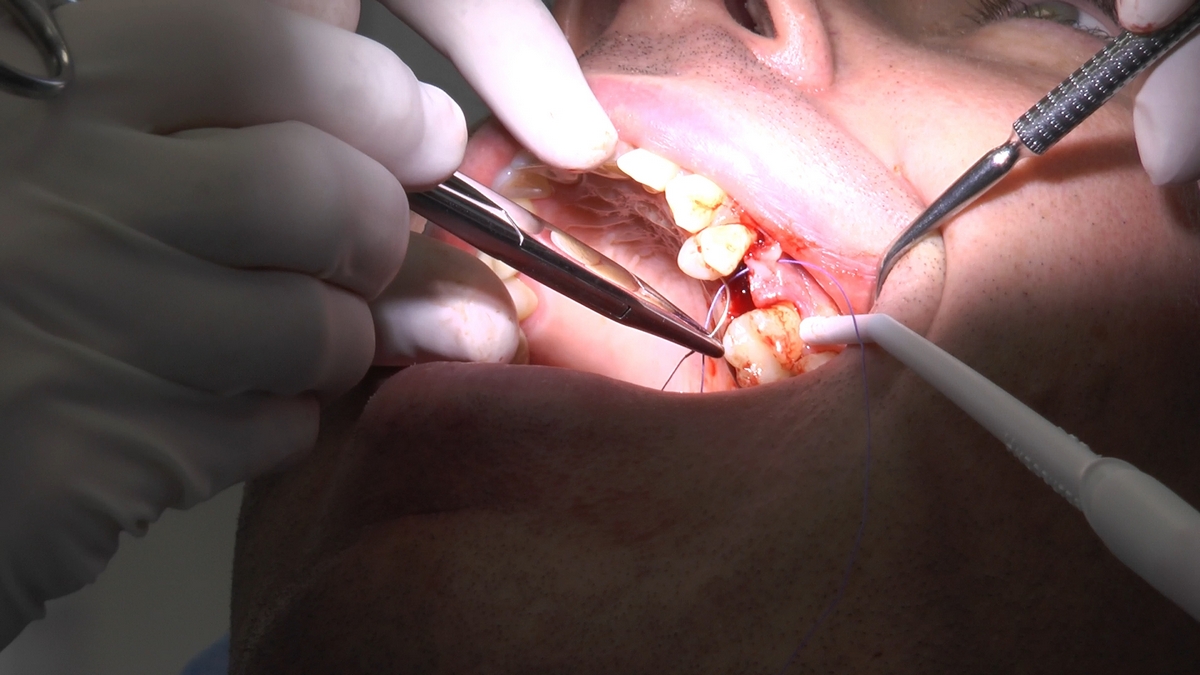

W trakcje dwóch dni zabiegowych, piątek i sobota, 5 i 6 października 2018 roku, lekarze uczestniczący w 6 Sesji VI Sezonu, wykonali wiele zabiegów o wysokim stopniu trudności. Przeprowadzili je pod kierunkiem Mentorów Instytutu Vivadental – dr n.med. Violetty Szycik, dr n.med. Magdaleny Kisłowskiej-Syryczyńskiej oraz dr Małgorzaty Piotrowskiej.

zabiegi regeneracji kości z zastosowaniem materiałów kościozastępczych i kości własnej oraz fibryny bogatopłytkowej,

zabiegi odsłonięcia 10 implantów wprowadzonych przez uczestników Practiculum,